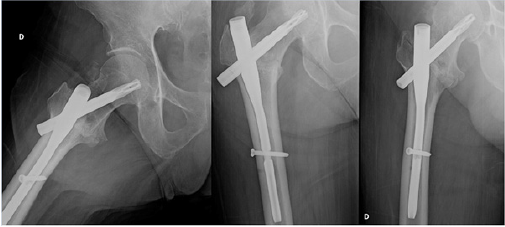

The patient was a 68 years old male, who had a car accident (Table 1). When he was admitted to the hospital, X-ray examination revealed a fracture of the surgical neck of left humerus and a fracture of the right femoral neck. He was treated with an intramedullary nailing of the femur (Proximal Femoral Nail Antirotation - PFNA system by ©DePuy Synthes) (Figure 1). The humerus fracture was managed conservatively with a shoulder immobilization for the first two weeks. The patient had an uneventful postoperative period, and he began immediately postoperative rehabilitation without weight bearing for the first two weeks. He continued his rehabilitation program in the following months, after hospital discharge, in a physiotherapy centre near his home. He placed on him from the third week, and two weeks later he has recovered to walk by himself, with the help of two crutches. At 6 months of follow-up, the Physicians (M.P., D.L.) noted a delayed healing of the fractures on X-ray (Figure 2), despite the good clinical condition of the patient, in fact he had no pain, and he was able to walk by himself without crutches or a limp. In addition, the patient missed the one-year follow-up due to pandemic emergency in March 2020. Two months after, he developed groin pain of the right hip and it was treated with a phone consultation by his general practitioner for a sciatic problem. Because of the persistent pain he called his surgeon who prescribed a new X-ray that revealed a superomedial migration of the proximal femoral blade, a phenomenon called cutin [12] (Figures 3 & 4). For this reason, the patient underwent a primary total hip arthroplasty with stem revision (©Lima Corporate) in October 2020 (Figure 5).

Figure 3: X-ray fourteen months after surgery and cut-in phenomenon.